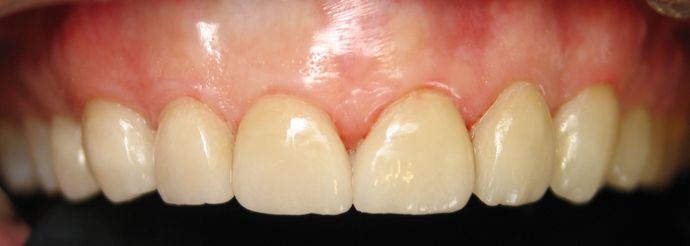

Porcelain Veneers: Patient #5

A long standing patient for Kansas City Dentist, John P. Goodman, DDS was seeking a solution to discoloration, extra spaces, and alignment issues in his upper 8 front teeth. Dr. Goodman combated these issues with durable custom fit and shaded Porcelain Veneers. Porcelain Veneers are completed within two visits, three if with an initial consultation as a new patient. On the first treatment visit, the teeth were prepped lightly and impressions were taken for the lab. During this visit, the patient and Dr. Goodman discussed the personalized shade and style for the appearance of the veneers. After about two weeks the final sparkling Porcelain Veneers were placed and the results were luminous! This patient and Dr. Goodman were both very happy with the finished look.